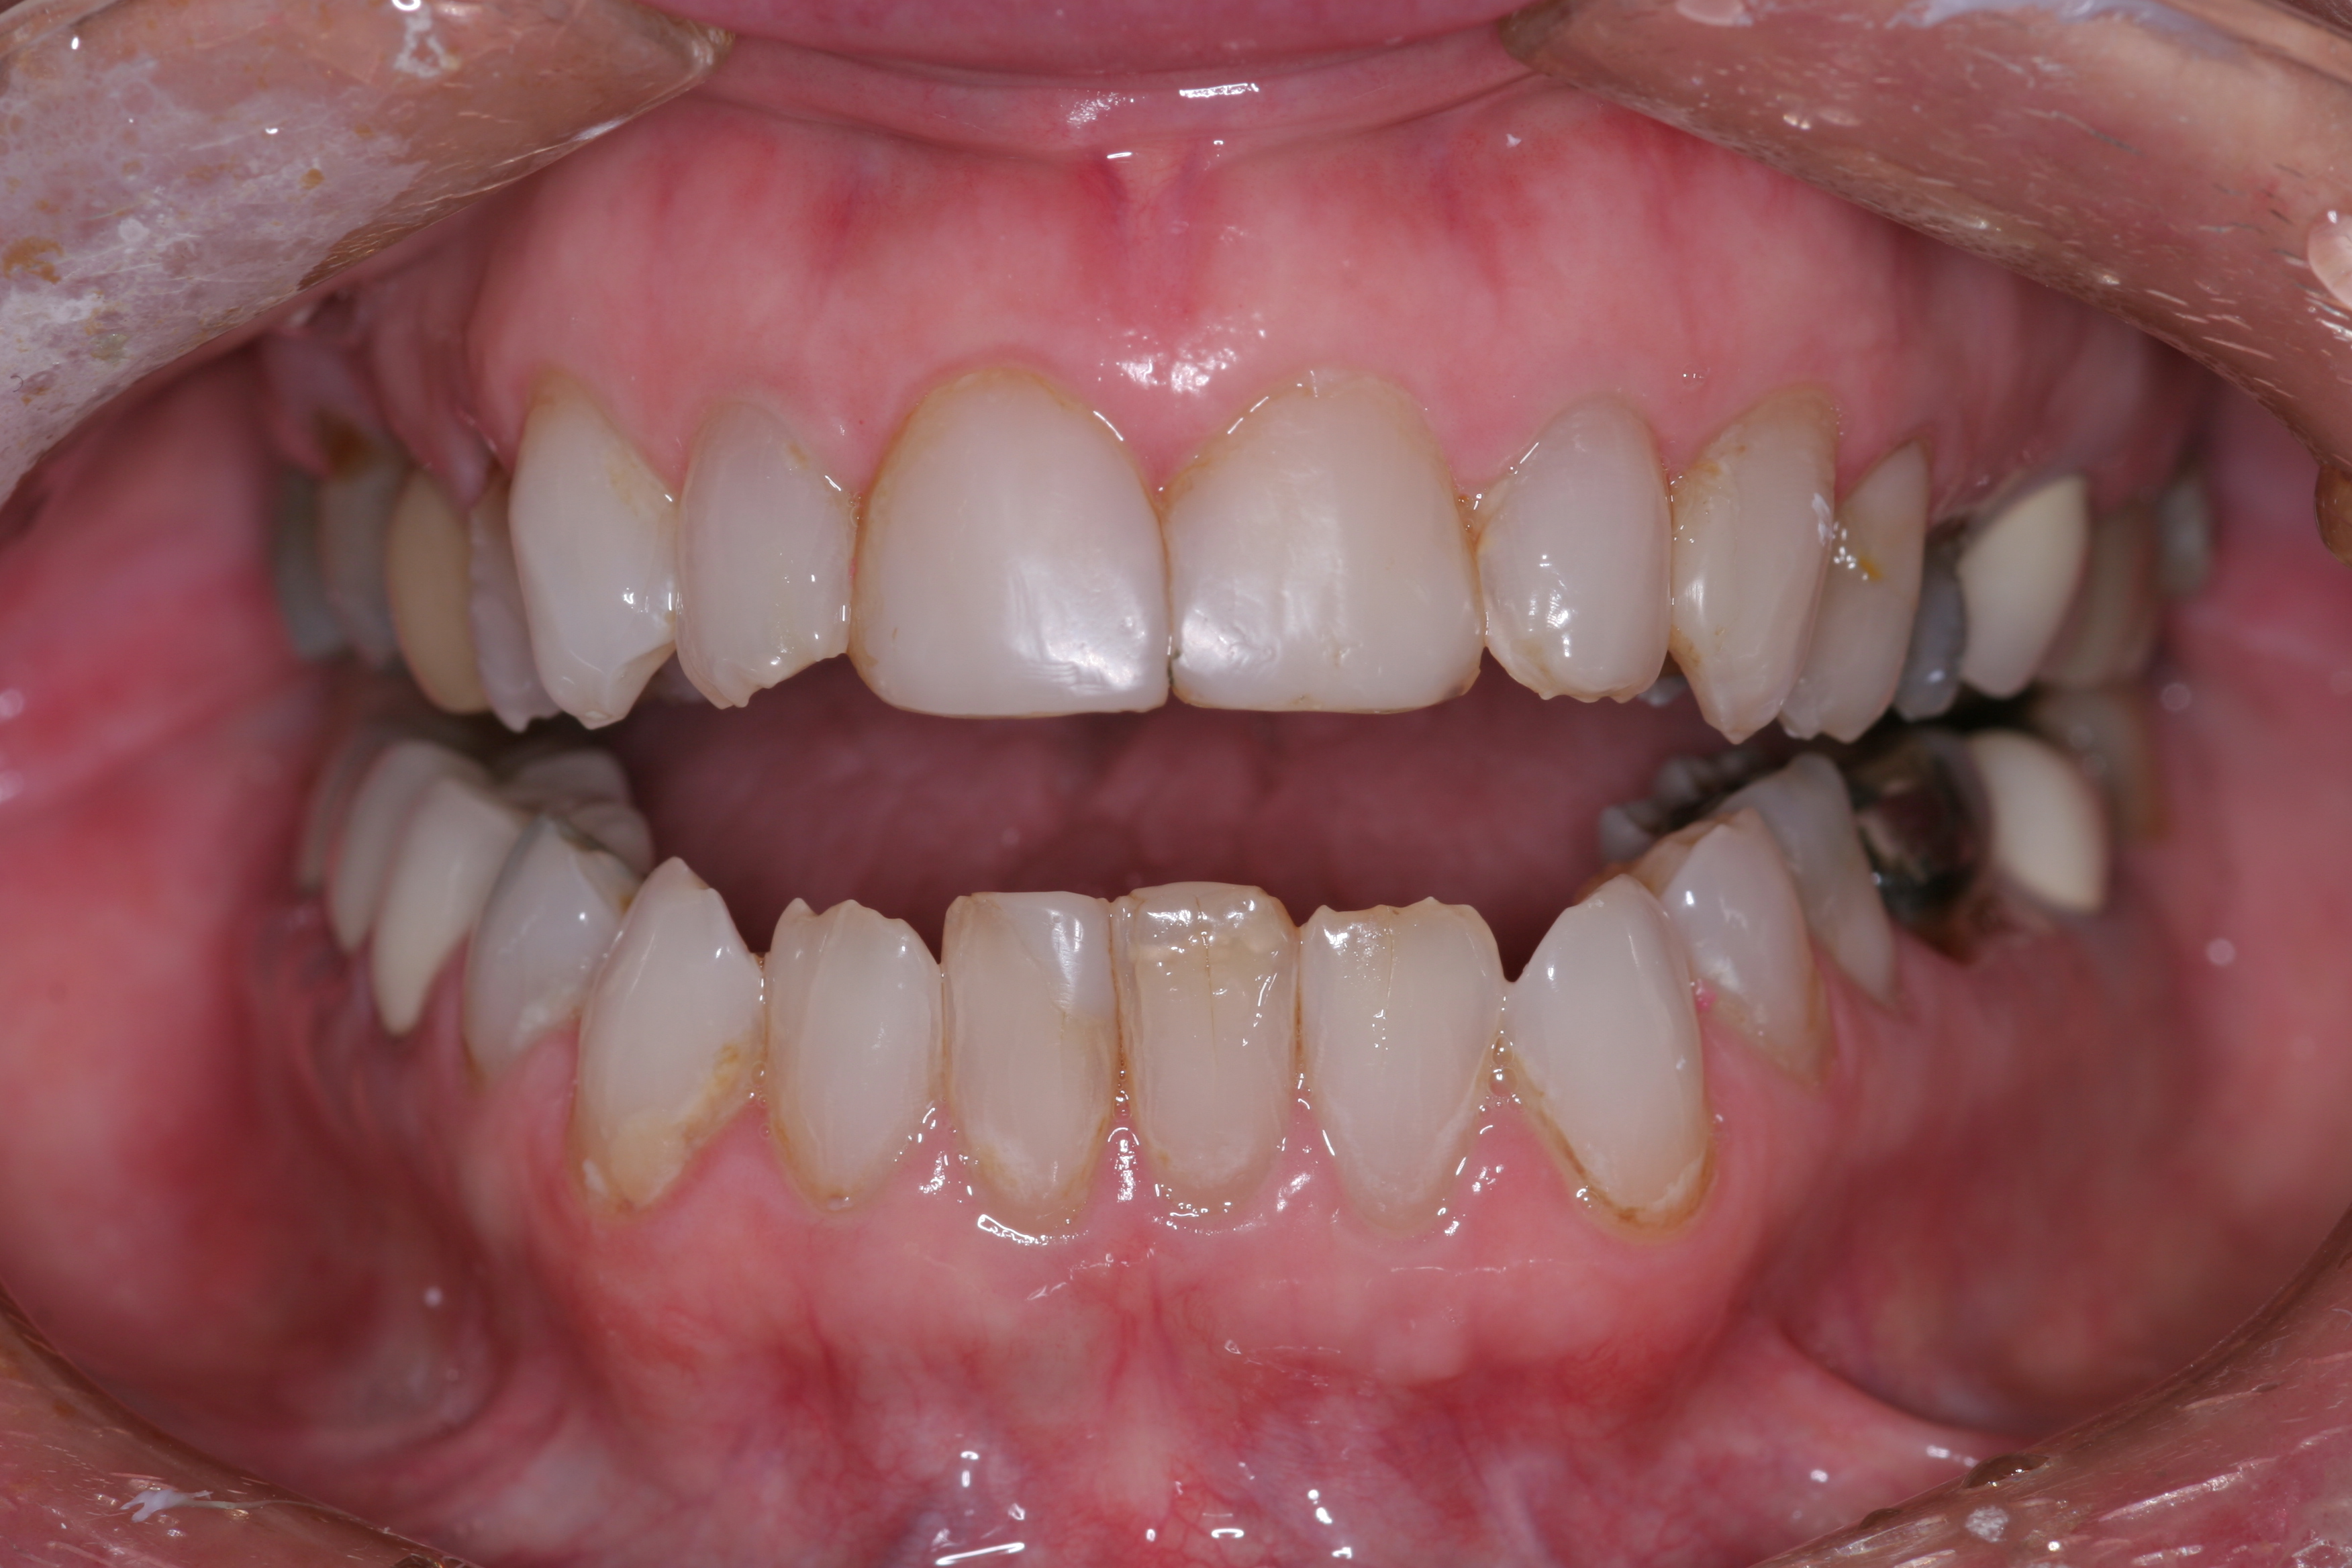

(11.) A patient presented with advanced generalized wear of her anterior teeth, and was displeased with their overall appearance because of their color and wear.

Figure 11

(12.) A patient presented with advanced generalized wear of her anterior teeth, and was displeased with their overall appearance because of their color and wear.

Figure 12

A patient presented with advanced generalized wear of her anterior teeth (Figure 10 and Figure 11). She was displeased with their overall appearance because of their color and wear (Figure 12). A complete examination was performed, revealing instability in her temporomandibular lateral poles bilaterally, sore muscles of mastication, advanced wear, a CR/MIP discrepancy, and loss of her anterior guidance due to the wear. Although the topic is beyond the scope of this article, the patient was also screened for possible sleep apnea. This included an evaluation of the Mallampati score, previous sleep therapy evaluation or treatment, snoring history, an evaluation of her neck size, her weight status, and the presence of the tonsils and their size. In every case, if this clinician suspects airway obstruction to be playing a role in tooth wear issues, the patient is referred to a sleep physician. The patient in this case displayed few apnea risk factors, and the patient’s anterior wear facets fit together like a “lock and key” pattern seen in parafunctional activity. Splint therapy was initiated to stabilize the joints and muscles. A repeatable CR position was verified through load testing. At this point diagnostic models, photographs, a CR bite record, and a facebow were taken and recorded.